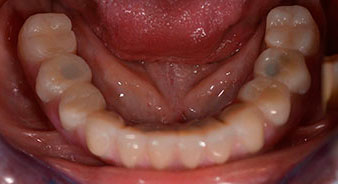

Die 64-jährige Patientin wurde mit einer Unterkiefer-Restbezahnung 38, 33 und 43 und einer klammerbefestigten Interimsprothese im Unterkiefer vorstellig (Abb. 1 und 2).

Unterkiefer-Restbezahnung

Abb. 1

Abb. 2